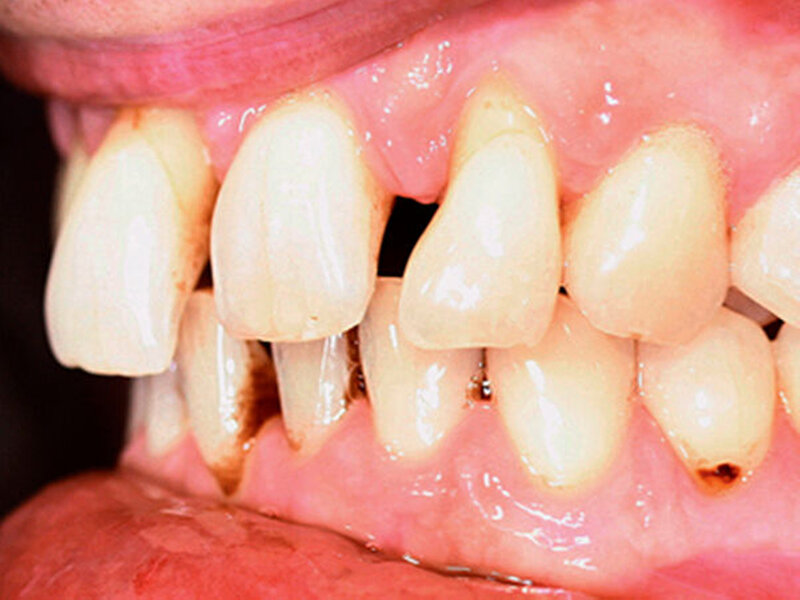

Anamnestisch lagen keine Besonderheiten vor. Es ist jedoch zu vermerken, dass ein regelmäßiger Alkohol-, Koffein- und Nikotinkonsum zugrunde lag. Intraoral zeigte sich ein bereits konservierend versorgtes permanentes Gebiss mit aktivem und inaktivem kariösen Geschehen. Große Anteile der Zahnhälse lagen nach Zahnfleischrückgang in Kombination mit Knocheneinbrüchen frei. Zahn 27 wurde bereits extrahiert.

Eine Beurteilung der parodontalen Situation an Zahn 11 offenbarte mesial und distal Sondierungstiefen von jeweils 6 mm.

Röntgenologisch stellte sich im Orthopantomogramm der bereits intraoral ersichtliche horizontale und vertikale Knochenabbau mit Attachmentverlust an einzelnen Zähnen dar. Die Erhaltungswürdigkeit einzelner Zähne war aufgrund des starken Knochenverlustes beziehungsweise der Beeinträchtigung des Halteapparates als kritisch zu beurteilen.

Zudem wurde die Diagnose einer Parodontitis gestellt, die eine Rücküberweisung an den Hauszahnarzt erforderlich machte (Abbildung 2).